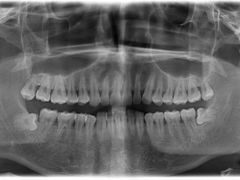

• 瑞尔齿科(上海长风大悦城店)

• -瑞尔齿科(上海长风大悦城店)